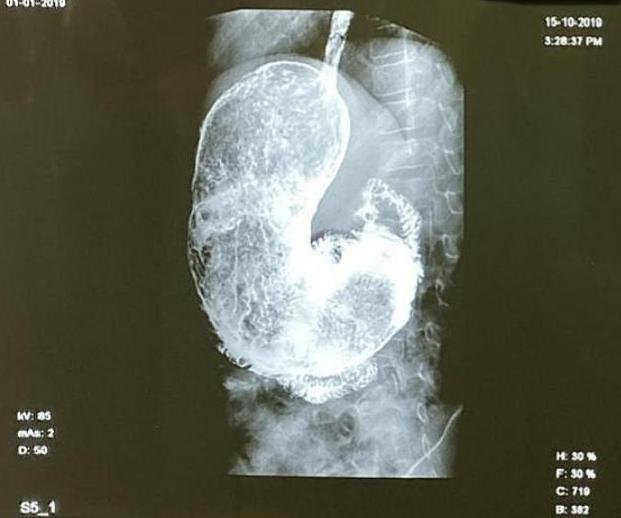

Шок: Не е за вярване какво откриха в стомаха на здраво 11-г. момченце СНИМКИ 18+